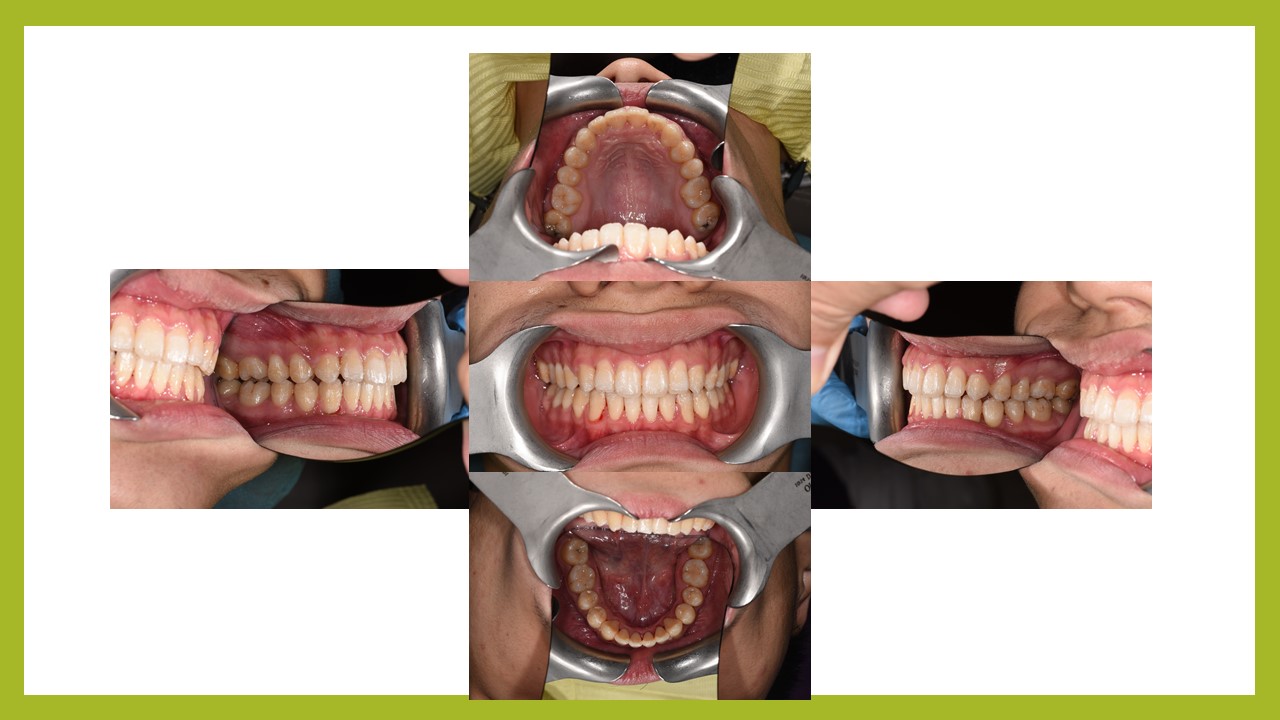

何先生因為有牙齒卡在裡面,去他家診所評估需要拔牙。後來經林醫師檢查過後,認為不須拔牙就可把牙齒排列整齊,何先生接受了不拔牙矯正。